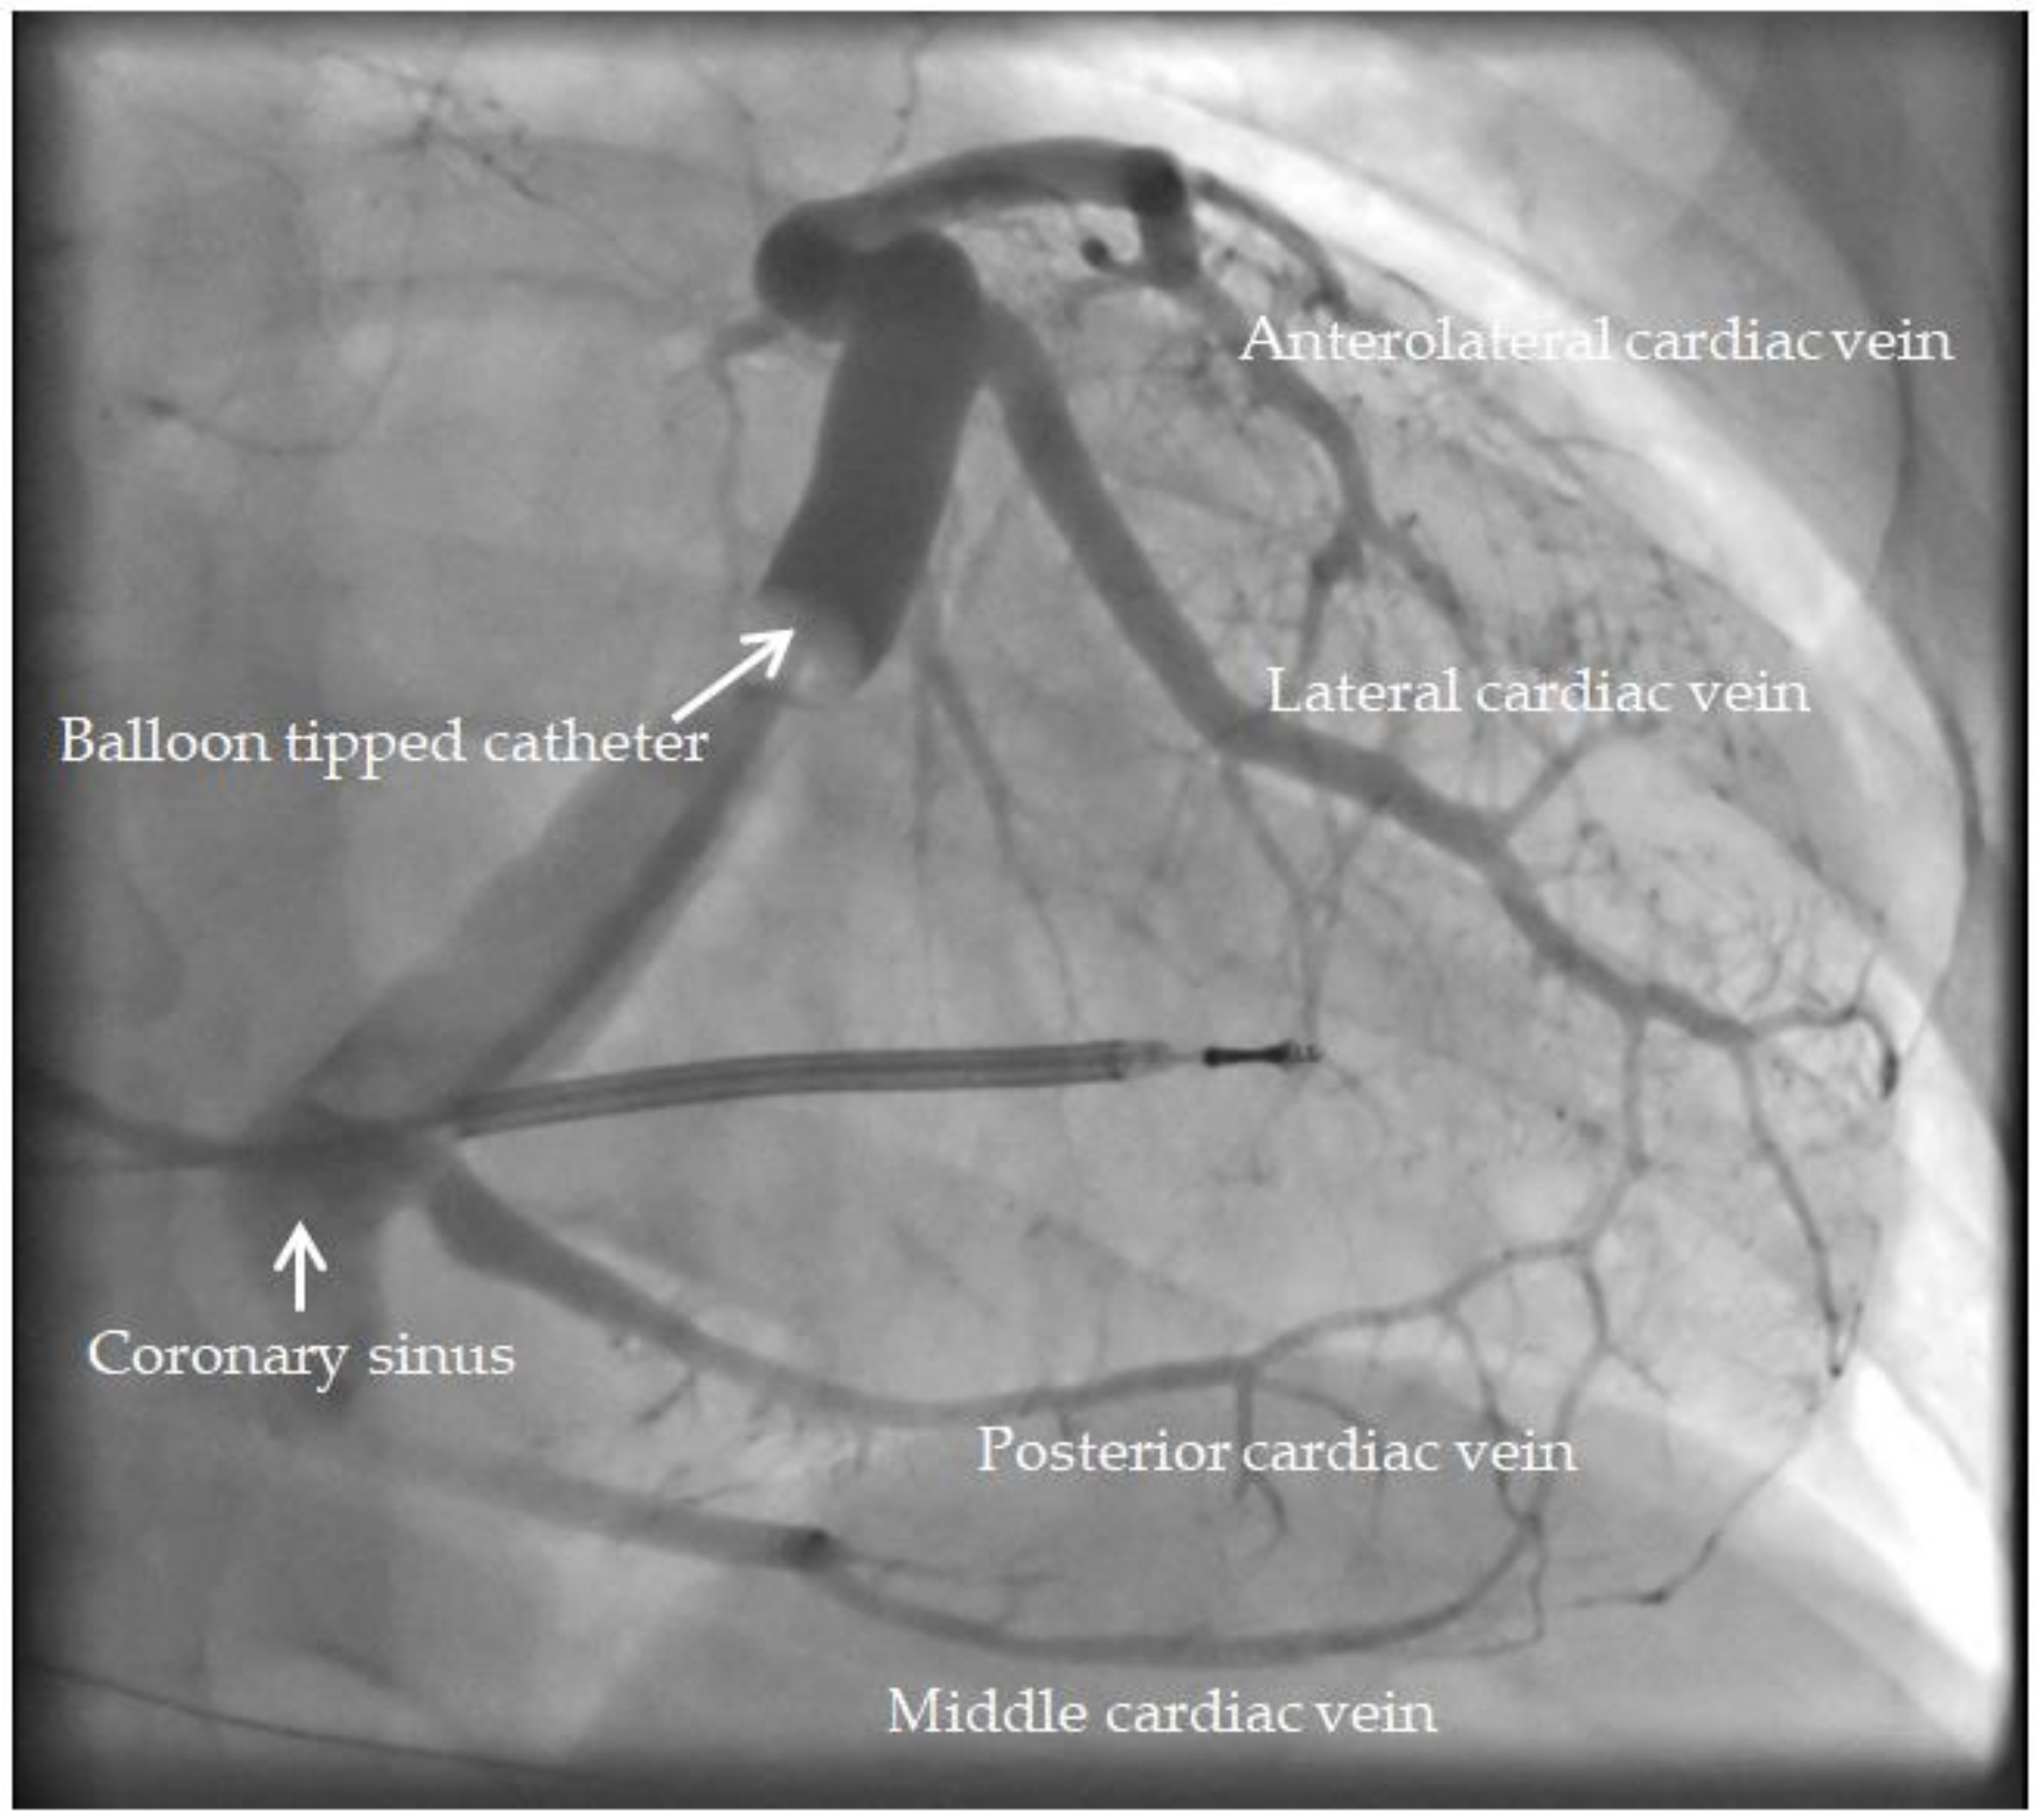

| Presence of coronary sinus branch | |

| Posterior vein | 8 (36.4) |

| Posterolateral vein | 11 (50.0) |

| Lateral vein | 22 (100) |

| Anterolateral vein | 14 (63.6) |

| Anterior vein | 18 (81.8) |

| Site of LV lead placement | |

| Posterior vein | 4 (18.2) |

| Posterolateral vein | 4 (18.2) |

| Lateral vein | 14 (63.6) |

| Anterolateral vein | 0 (0) |

| Anterior vein | 0 (0) |